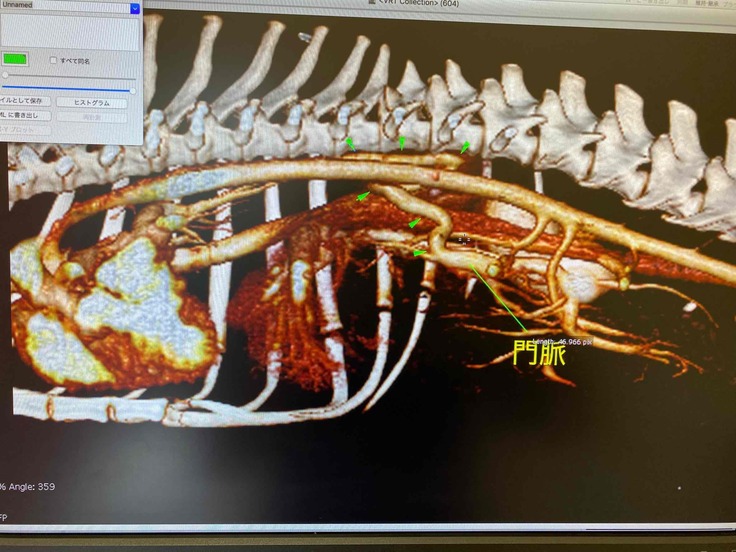

2021年9月21日に全身麻酔で行ったCT検査の結果

(CT検査はセカンドオピニオンから紹介された、CT専門の病院にて撮影)

結果、血液検査とCT検査で門脈シャントと診断されました。

また、CT検査でも膀胱内の結石をはっきりと確認できました。